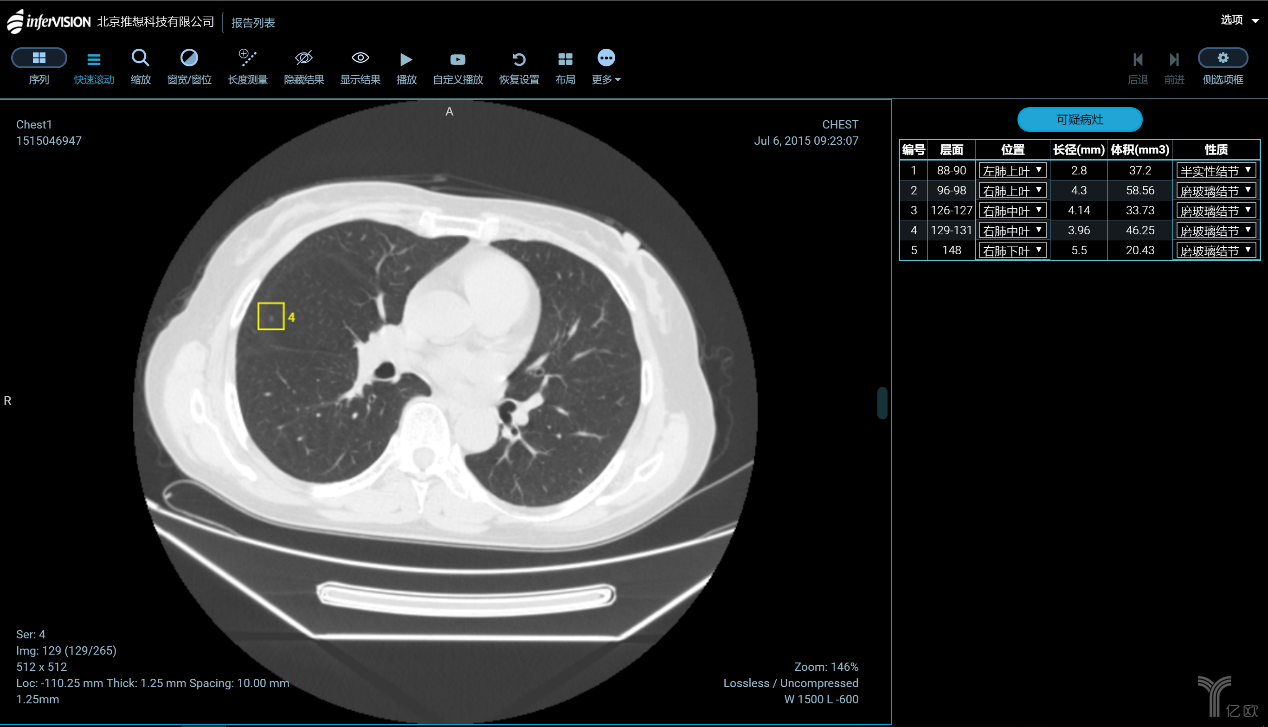

肺結(jié)節(jié)的識別與診斷,是大部分企業(yè)算法模型訓(xùn)練的起點。一方面是因為中國是肺癌大國,肺部影像數(shù)據(jù)量最充足;另一方面是由于全球針對肺結(jié)節(jié)識別的研究最為成熟。國內(nèi)在肺癌診斷與篩查方向進展較快的,主要有推想科技、圖瑪深維、健培科技、體素科技、依圖醫(yī)療、匯醫(yī)慧影、深睿醫(yī)療、視見醫(yī)療、華潤萬里云、零氪科技等。除了肺癌之外,針對乳腺癌、肝癌、鼻咽癌、腦卒中的自動檢測也正在成為焦點。

智能CT輔助篩查產(chǎn)品(AI-CT)功能界面(圖片來源:推想科技)